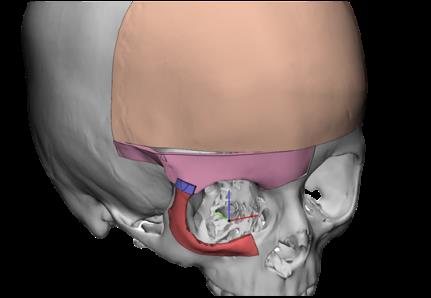

Chirurgia Oro-Mascellare per riabilitazioni protesiche post oncologiche

I pazienti che per motivi oncologici o per esito di osteonecrosi per uso di farmaci della categoria bifosfonati (in uso nelle gravi forme di osteoporosi o nel trattamento coadiuvante delle metastasi ossee)hanno subito gravi demolizioni dei mascellari e conseguente perdita della funzionalità masticatoria necessitano di ricostruzione e rifunzionalizzazione dell'apparato masticatorio con ricostruzione dell'osso mandibolare o del mascellare superiore attraverso innesti di osso , di lembi mucosi e/o muscolari di vicinanza ed a volte di implantologia preprotesica con impianti zigomatici , pterigoidei o convenzionali , tutto cio'con il fine di ripristinare una corretta funzione ma anche una auspicabile vita di relazione.

![]() | ![]() | ![]() | ![]() |

![]() | ![]() | ![]() |